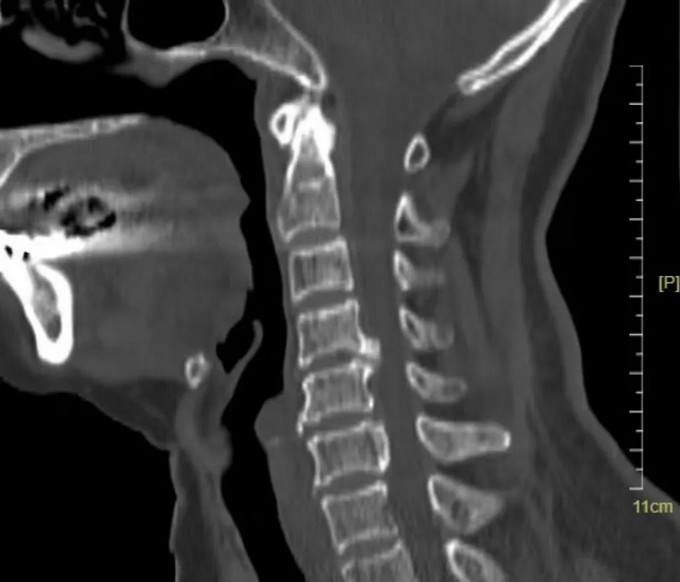

术前影像

颈椎CT矢状位

颈椎CT横断位 可以看到明显突出的骨赘